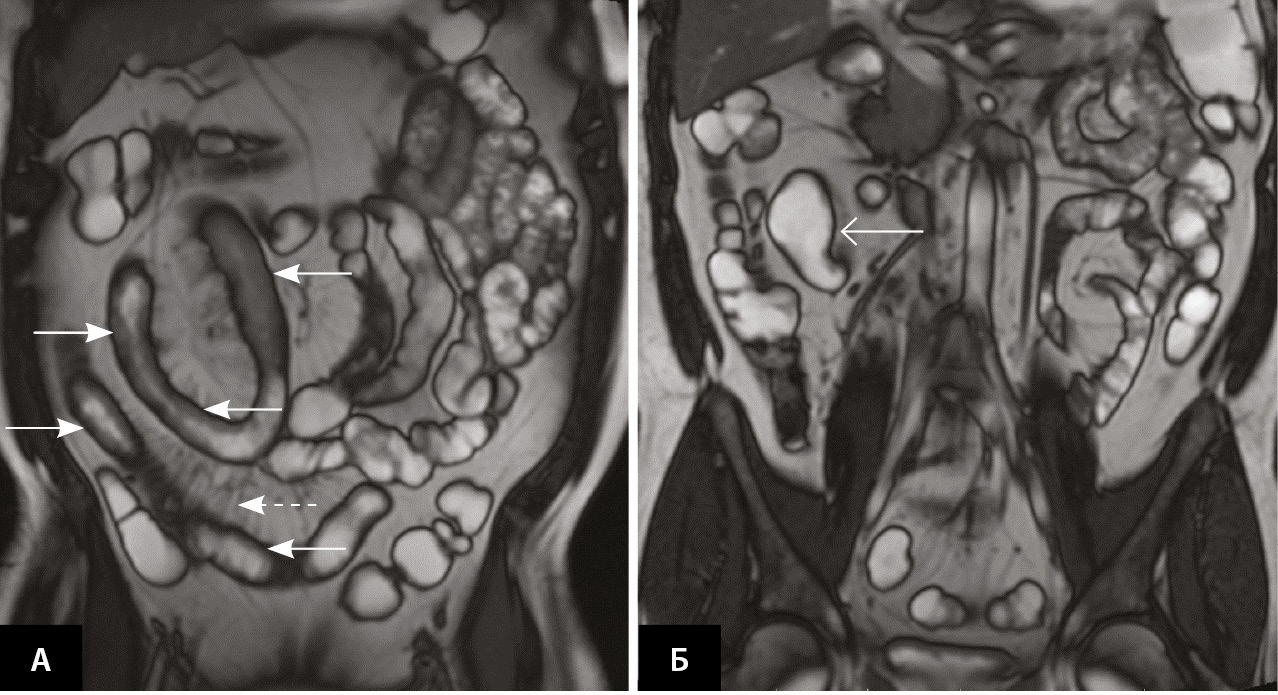

В начале февраля 2021 г. терапия адалимумабом была отменена, 17.02.2021 инициирована терапия канакинумабом 150 мг 1 раз в 4 недели подкожно и снижена доза колхицина до 1,5 мг в сутки. На этом фоне пациент отметил полное прекращение атак ССЛ. После отмены адалимумаба через несколько месяцев стали рецидивировать эпизоды динамической кишечной непроходимости. Пациент отказывался от проведения хирургического лечения и в течение последующих 2 лет продолжал наблюдаться у гастроэнтеролога. Периодически на фоне болевого синдрома в анализах отмечалось повышение СРБ. Получал курсами метронидазол, преднизолон внутривенно, с временным положительным эффектом. Продолжалась также терапия канакинумабом 1 раз в 4 недели с полным контролем атак ССЛ. В апреле 2022 г. выполнена энтероскопия, выявлены единичные эрозии проксимального отдела подвздошной кишки, множественные язвы терминального отдела подвздошной кишки, стриктура илеоцекального клапана (рис. 2). Пациент согласился на оперативное вмешательство.

Рис. 2. Энтероскопия от 08.04.2022: множественные сливающиеся эрозии и язвы под фибрином (сплошная стрелка), участки гиперемии слизистой оболочки в терминальном отделе подвздошной кишки (пунктирные стрелки)